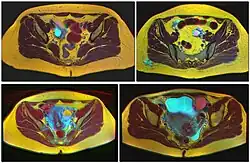

Four kinds of ovarian cysts on MRI

Ovarian cysts are usually diagnosed by pelvic ultrasound, CT scan, or MRI, and correlated with clinical presentation and endocrinologic tests as appropriate.[15] Ultrasound is the most important imaging modality, as abnormalities seen in a CT scan sometimes prove to be normal in ultrasound.[5][8] If a different modality is needed, then MRIs are more reliable than CT scans.[5]